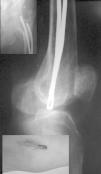

Figura 4. Migración distal con protrusión a través de la piel (imagen pequeña abajo a la izquierda) en una fractura con tan sólo dos clavos, que no rellenaban el canal medular de forma adecuada.

Extracción del material de osteosíntesis

Se realizó la extracción del material de osteosíntesis (AMO) en 55 casos (15%). Cuarenta y cinco pacientes por migración distal con repercusión clínica (fig. 4), 3 pacientes por migración distal asintomática y 7 pacientes por migración proximal sintomática. El tiempo medio hasta la AMO fue de 44 semanas, con dos momentos de máxima incidencia en torno a los 3 meses y al año. En 20 de los 55 casos, las molestias que indicaron la intervención persistieron tras la retirada de los clavos (tabla 1).